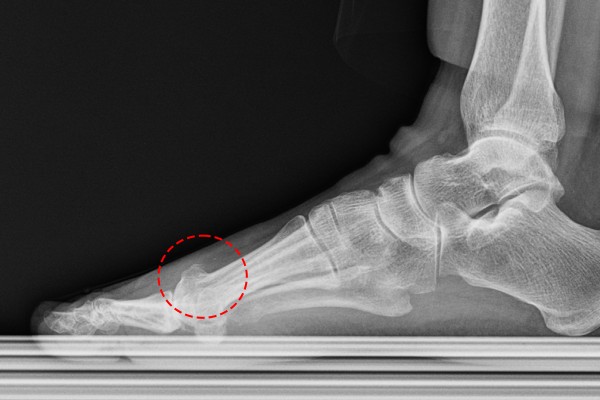

측면에서 촬영한 X-RAY 사진을 보면 우측 발에 골극이 자라나 있는 것이 확인됩니다.

반면, 좌측 발에는 골극이 보이지 않습니다.